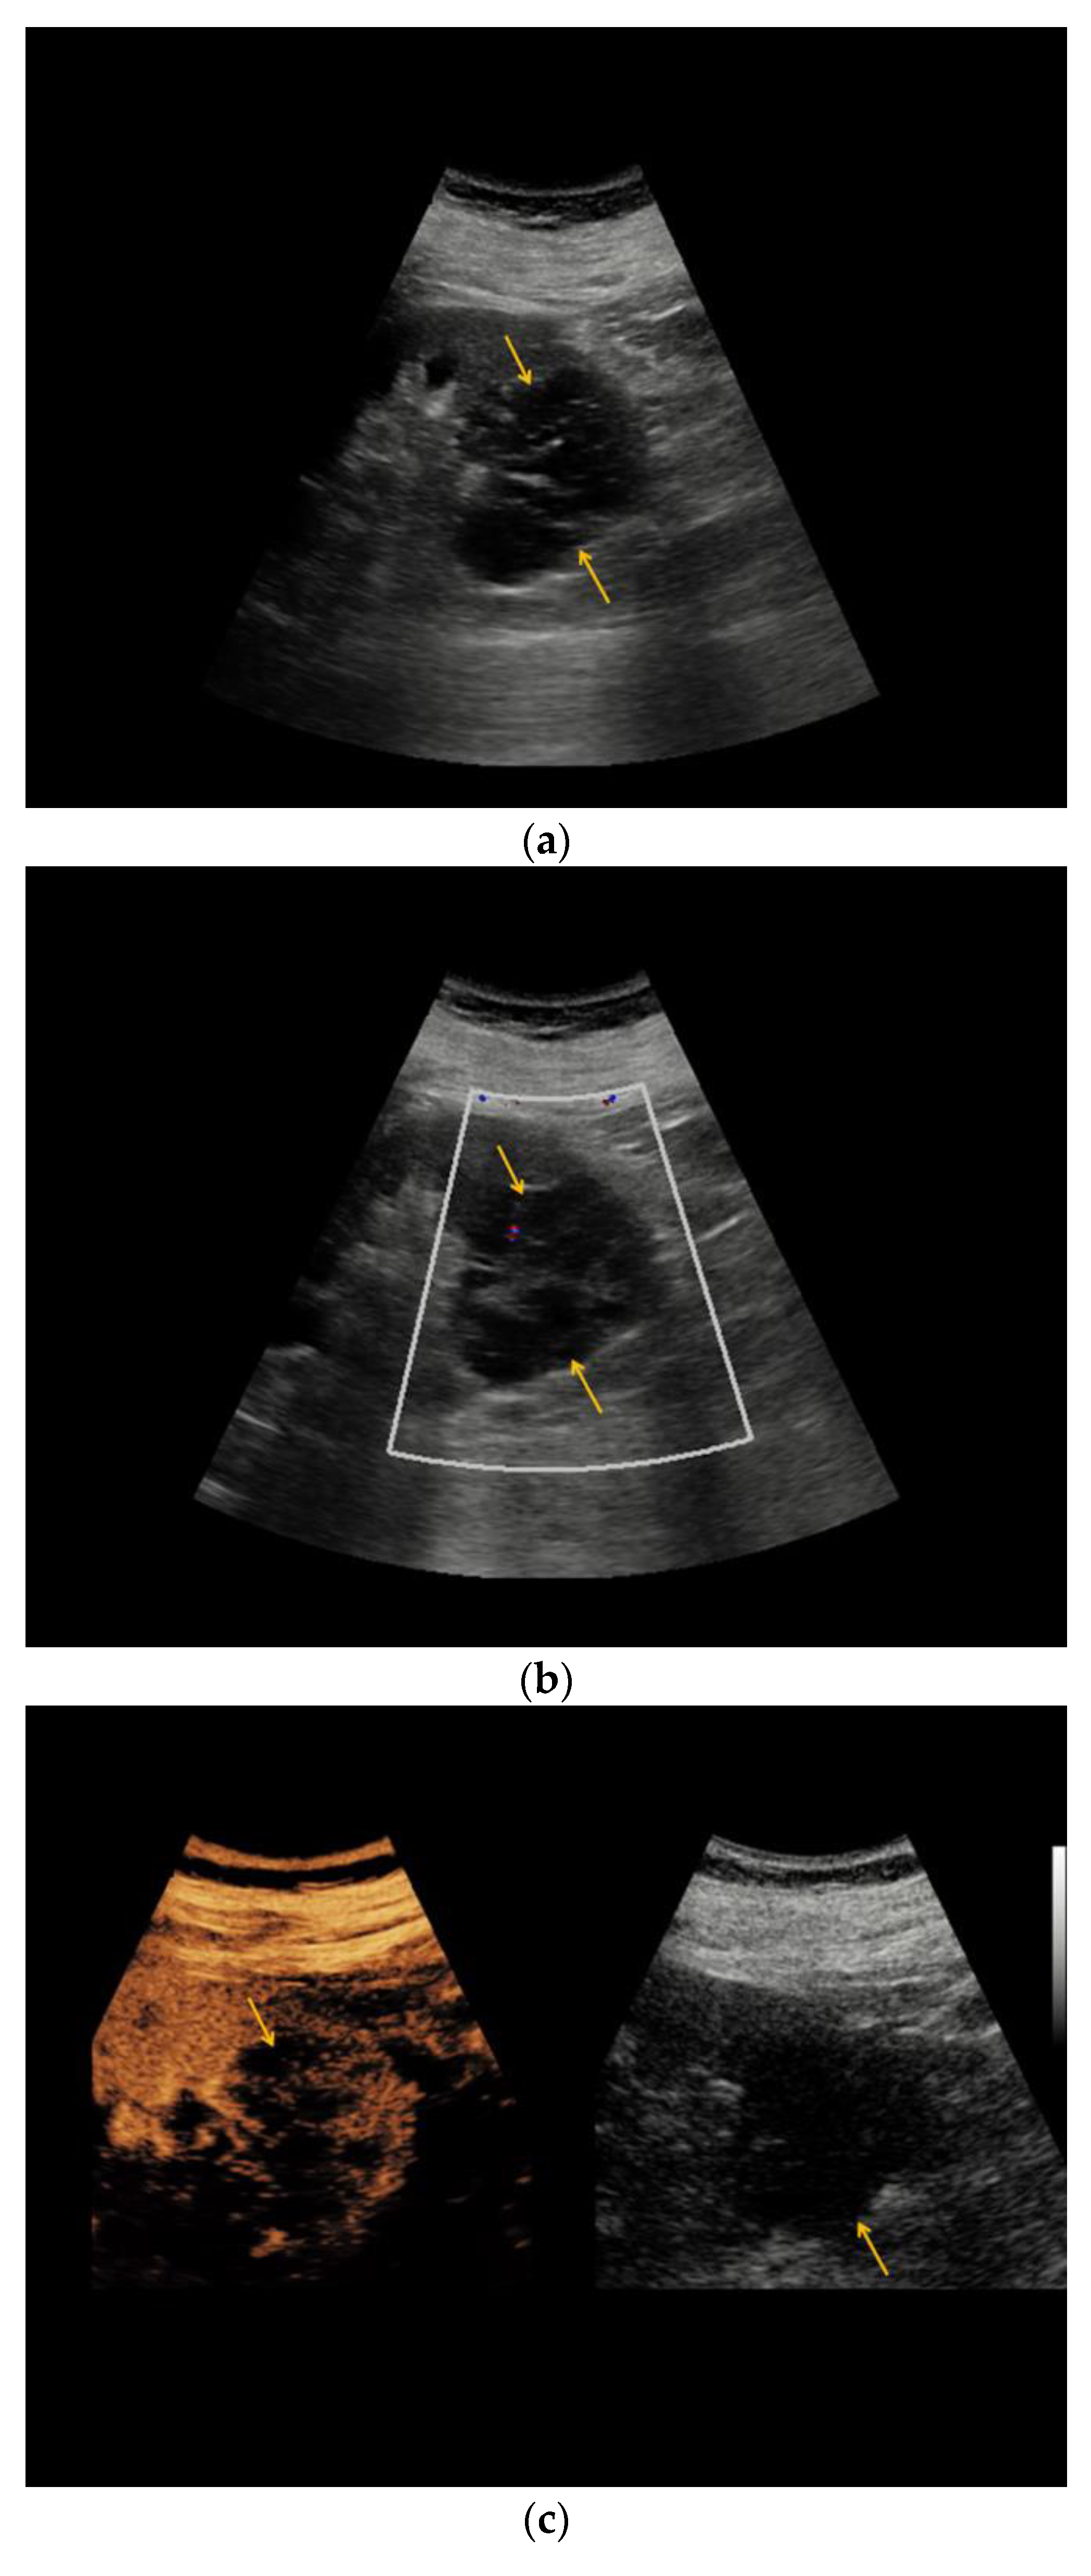

| Patient | Sex | Age | Location | Size (cm) | Native B-Mode | Vascularization (CD) | CEUS | CT | MRI | Treatment: Histopathology |

|---|---|---|---|---|---|---|---|---|---|---|

| #1 | F | 49 | R | 5.6 | Cystic, septated | - | Intraseptal | - | Intraseptal enhancing → Bosniak IIF | Partial nephrectomy: Clear-cell RCC |

| #2 | M | 54 | L | 3.0 | Cystic, hypoechoic areas, wall thickening | - | Peripheral | - | - | Partial nephrectomy: chromophobe RCC |

| #3 | F | 61 | R | 3.5 | Cystic, septated | - | Peripheral, intraseptal | - | - | Partial nephrectomy: clear-cell RCC |

| #4 | F | 43 | R | 1.6 | Cystic | - | Peripheral | - | - | Partial nephrectomy: clear-cell RCC |

| #5 | F | 64 | L | 5.0 | Cystic, focally thickened, septa | - | Intraseptal | - | - | Partial nephrectomy: clear-cell partial cystic RCC |

| #6 | M | 74 | L | 2.0 | Cystic | - | Peripheral, intraseptal | - | - | Partial nephrectomy: clear-cell RCC |

| #7 | F | 66 | L | 7.0 | Cystic, complex | - | Intraseptal | - | - | Partial nephrectomy: multilocular cystic RCC |

| #8 | M | 54 | L | 1.5 | Cystic, wall thickening | - | Intraseptal | - | - | Partial nephrectomy: clear-cell RCC |

| #9 | M | 76 | L | 1.6 | Cystic | - | Peripheral, wash-out | - | - | Partial nephrectomy: papillary RCC |

| #10 | F | 66 | R | 1.5 | Cystic | - | Intraseptal | - | - | Partial nephrectomy: clear-cell RCC |

| #11 | M | 75 | L | 2.7 | Cystic, focally thickened septa | - | Intraseptal | - | - | Partial nephrectomy: Papillary RCC |

| #12 | M | 52 | L | 1.5 | Cystic, focally thickened septa | - | Intraseptal | - | - | Partial nephrectomy: clear-cell RCC |

| #13 | M | 68 | L | 1.5 | Partially cystic | - | Peripheral | - | - | Partial nephrectomy: clear-cell RCC |

| #14 | M | 86 | L | 4.0 | Cystic, septated | - | Intraseptal | Septated, calcified, early enhancement, wash-out in delayed phase → Bosniak III | - | Nephrectomy: cystic clear-cell RCC |

| #15 | M | 63 | R | 2.0 | Cystic | - | Peripheral | - | - | Nephrectomy: clear-cell RCC |

| #16 | F | 62 | L | 2.5 | Partially cystic | - | Peripheral, intraseptal wash-in/wash-out | - | Native MRI: T2w: mainly hyperintense with hypointense septations T1w: hypointense | Renal biopsy: oncocytoma |

| #17 | F | 64 | R | 3.5 | Cystic | - | Intraseptal | - | - | Partial nephrectomy: cystic hamartoma |

| #18 | M | 67 | R | 3.0 | Partially cystic, focally thickened septa | - | Intraseptal | - | - | Partial nephrectomy: cyst, no malignancy |

| #19 | M | 71 | L | 1.2 | Cystic | - | Peripheral | - | - | Partial nephrectomy: cyst, no malignancy |

| #20 | F | 48 | L | 10.0 | Cystic, septated | - | Intraseptal | - | - | Partial nephrectomy: adult cystic nephroma |

| #21 | M | 76 | R | 2.0 | Cystic | - | Peripheral and Intraseptal wash-in/wash-out | - | - | Partial nephrectomy: oncocytoma |

| #22 | M | 46 | R | 0.8 | Cystic | - | Peripheral wash-in/wash-out | - | - | Partial nephrectomy: papillary adenoma |

| #23 | F | 69 | L | 8.0 | Cystic, septated | - | Intraseptal | - | - | Partial nephrectomy: cyst, no malignancy |

| #24 | M | 69 | R | 2.5 | Cystic | - | Peripheral wash-in/wash-out | - | - | Partial nephrectomy: Papillary RCC |

| #26 | M | 66 | R | 5.0 | Cystic | - | Peripheral | - | - | Partial nephrectomy: Hemorrhagic, xantho-granulomatous cyst, no malignancy |

| #27 | M | 67 | R | 7.0 | Cystic, septated, partially calcified | - | Peripheral, intraseptal | Septated, partially calcified → Bosniak IIF | - | Partial nephrectomy: oncocytoma |

| #32 | M | 83 | L | 4.7 | Cystic | - | Peripheral | - | - | Partial nephrectomy: clear-cell RCC |

| #35 | M | 48 | R | 2.5 | Cystic, septated | - | Intraseptal wash-in/wash-out | - | - | Partial nephrectomy: clear-cell RCC |

| #38 | M | 60 | R | 1.2 | Cystic, septated | - | Peripheral | Septated, contrast-enhanced → Bosniak type IIF | - | Partial nephrectomy: clear-cell RCC |